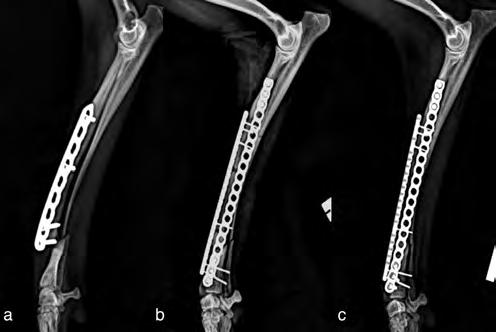

Figura 1. Comparativa en 3D de ambas extremidades con la correspondiente deformidad.

Figura 2. Simulación en 3D de la ostectomía correctiva que se ha de realizar según el software, una vez obtenido el CORA.

ocupa, además de las radiografías postoperatorias realizadas tras la cirugía correctiva y las efectuadas antes de retirar los implantes, se realizó una TC de revisión tras la extracción de los mismos (al año y dos meses de su colocación), observándose en 3D una buena remodelación y alineación de los huesos. Si comparamos estas imágenes de TC con las primeras, es decir, con las de la planificación quirúrgica antes de la corrección, se puede observar que la superposición de ambas TC muestra una alta precisión en lo que respecta al resultado obtenido (Fig. 8).

Figura 8. (A) Reconstrucción en 3D de los huesos del antebrazo afectado antes de realizar la ostectomía y colocar los implantes y (B) después de retirarlos.